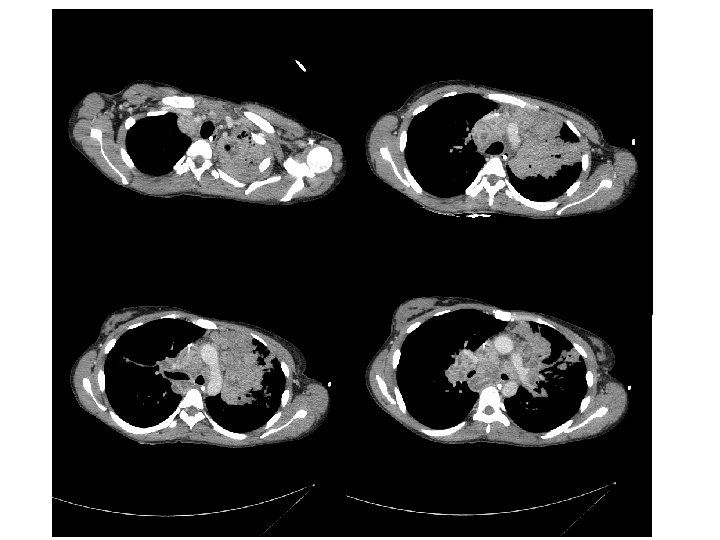

Evolution… Reste fébrile 39 -41°C 22/06: Fibroscopie bronchique 28/06: Antibiothérapie à large spectre 28/06 (J 17)Corticothérapie interrompue car absence d’amélioration • 15/07: Fibroscopie bronchique, TDM TAP • •

• 30/07: Reprise de la corticothérapie à 2 mg/kg/j pendant 21 j puis 1, 5 mg/kg/j • Vérification de la bonne observance thérapeutique • Antituberculeux par voie IV • Taux sériques antituberculeux normaux • Accalmie…avec une température qui diminue (38 -39°C) • Sortie le 20/08